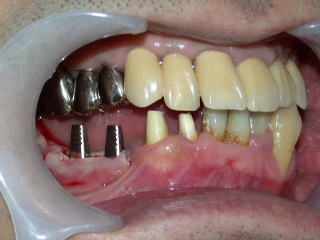

平成20年3月、インプラントの植立を行いました。

上下の隙間(補綴スペース)や近遠心、頬舌関係を良く調べます。

顎の上下関係、全体の位置付けも重要です。

目視で良く確認、レントゲンで位置をさらに良く確認します。

インプラントの位置が、良い位置に植立されたのを確認し、4糸縫合しました。

インプラント固定用の仮歯を装着し、抗生物質などを処方し、インプラント植立を終了します。